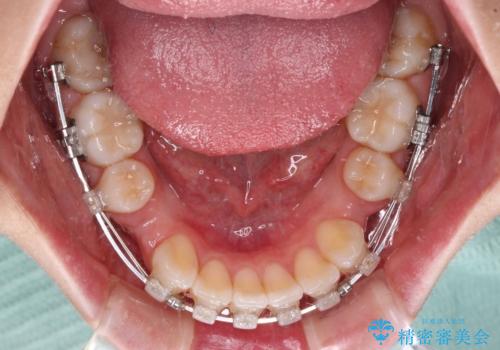

- クリアブラケット

- 1年6ヶ月

- 前歯の出っ歯と口元の閉じにくさを気にして来院された患者様です。

口元を積極的に引っ込めるために、上下左右の小臼歯4本を抜歯することとしました。

4本の歯を抜歯したことで、飛び出していた口元が引っ込み、横顔が大きく改善されました。